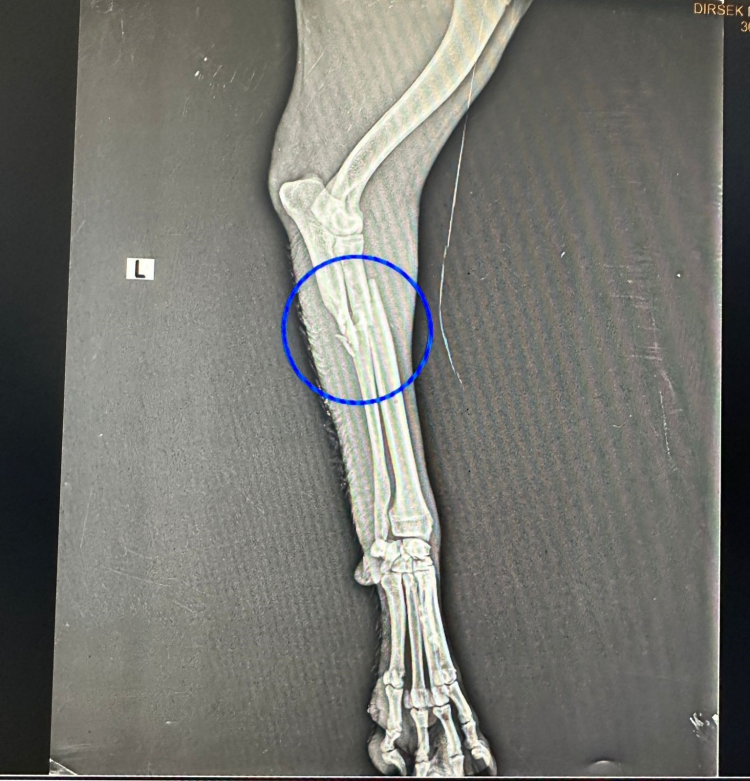

Sol ön ayağının kırıldığı belirlenen köpeğin ayağı alçıya alındı. Gerekli tedavileri yapılan yaralı köpek, sağlığına kavuşana kadar Kızıltepe Belediyesi korumasında kalacağı açıklandı.